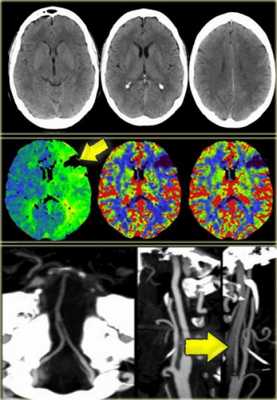

Пенумбра: Окклюзия в СМА. Черным указано ткань с необратимыми изменениями или мертвая ткань. Красным выделена ткань-риска или пенумбра.

КТА и КТ-перфузия.

После того, как лучевой диагност обнаружил область ишемии, используя КТ-ангиографию ищет тот сосуд, который вовлечён в патологический процесс.

В данном случае признаки инфаркта едва уловимые. Гиподенсная зона в островковой области справа. В данном случае эти изменения соответствуют инфаркту, но у пожилых пациентов с лейкоэнцефалопатией тяжело отдифференцировать эти две разные патологии.

Вышележащие изображения — КТ-ангиография. После выполнения КТА — диагноз инфаркта в области СМА, как на ладоне.

КТ-перфузия (КТП).

При использовании КТ и МРТ-диффузии мы можем с уверенностью найти ту зону, которая ишемизирована, но не сможем сказать о зоне большой ишемической пенумбры (ткань риска).

При помощи перфузии можем ответить на вопрос, какая ткань находится в риске. По статистике 26% пациентам следовало бы выполнить перфузию для уточнения диагноза. Возможности МРТ перфузии и КТ сопоставимы.

Было проведено исследование для сравнения КТ и МРТ, при котором было установлено, что для выполнения КТ, КТА и КТП при условии, что у вас хорошо сложенная команда, требуется 15 минут. В данном случае была выполнена только КТ так, как выявлено кровоизлияние. В этом случае изначально выполнены КТ без контрастирования и КТ-перфузия так, как выявлен дефект перфузии было целесообразно выполнение КТ-ангиографии, на которой выявлено диссекция левой внутренней артерии.